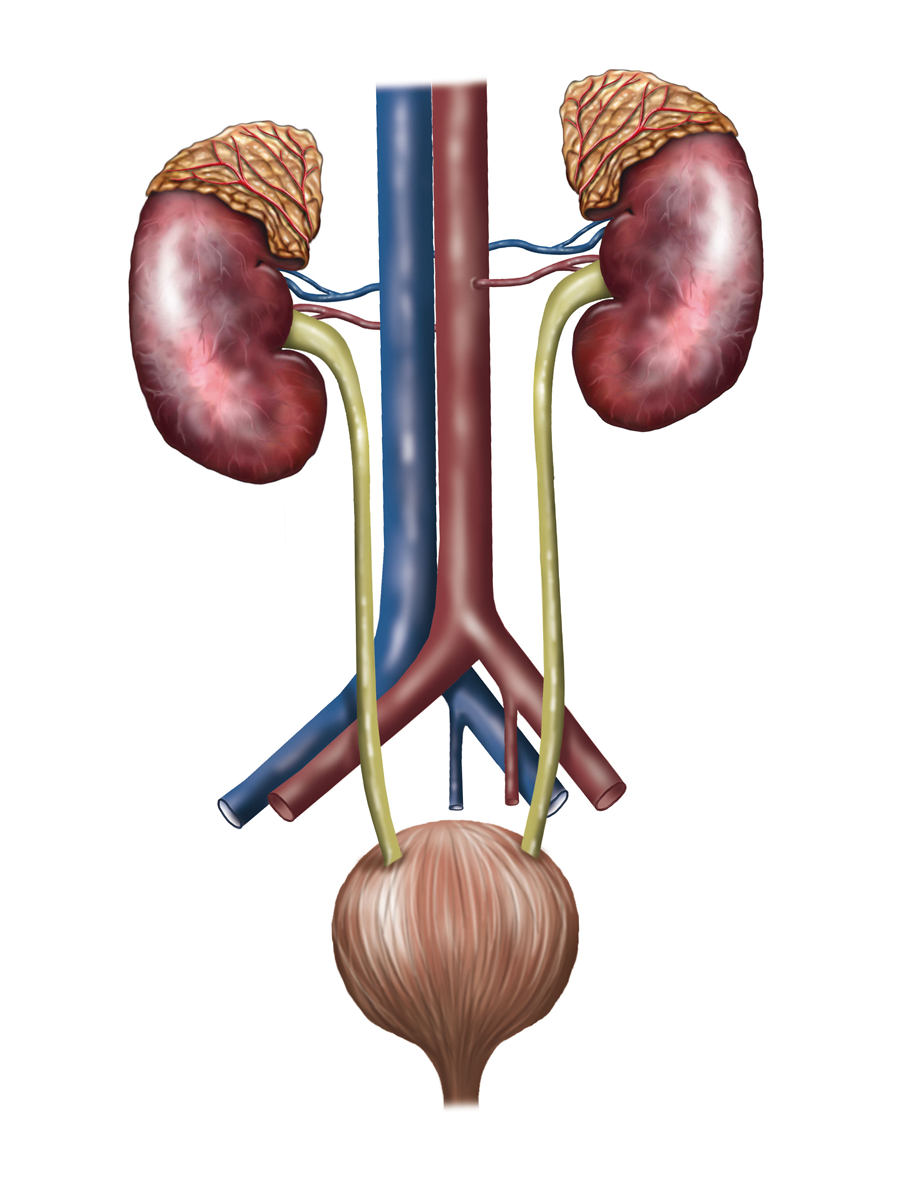

Herzlich willkommen! Ich bin Ihre Expertin für medizinische Illustrationen und kreative Kinderbuch-Illustrationen. Mit einem Auge für wissenschaftliche Genauigkeit und einer Liebe zur Gestaltung kindgerechter Erzählwelten schaffe ich Bilder, die informieren und begeistern. Entdecken Sie mein Portfolio und lassen Sie sich von meiner Arbeit überzeugen!